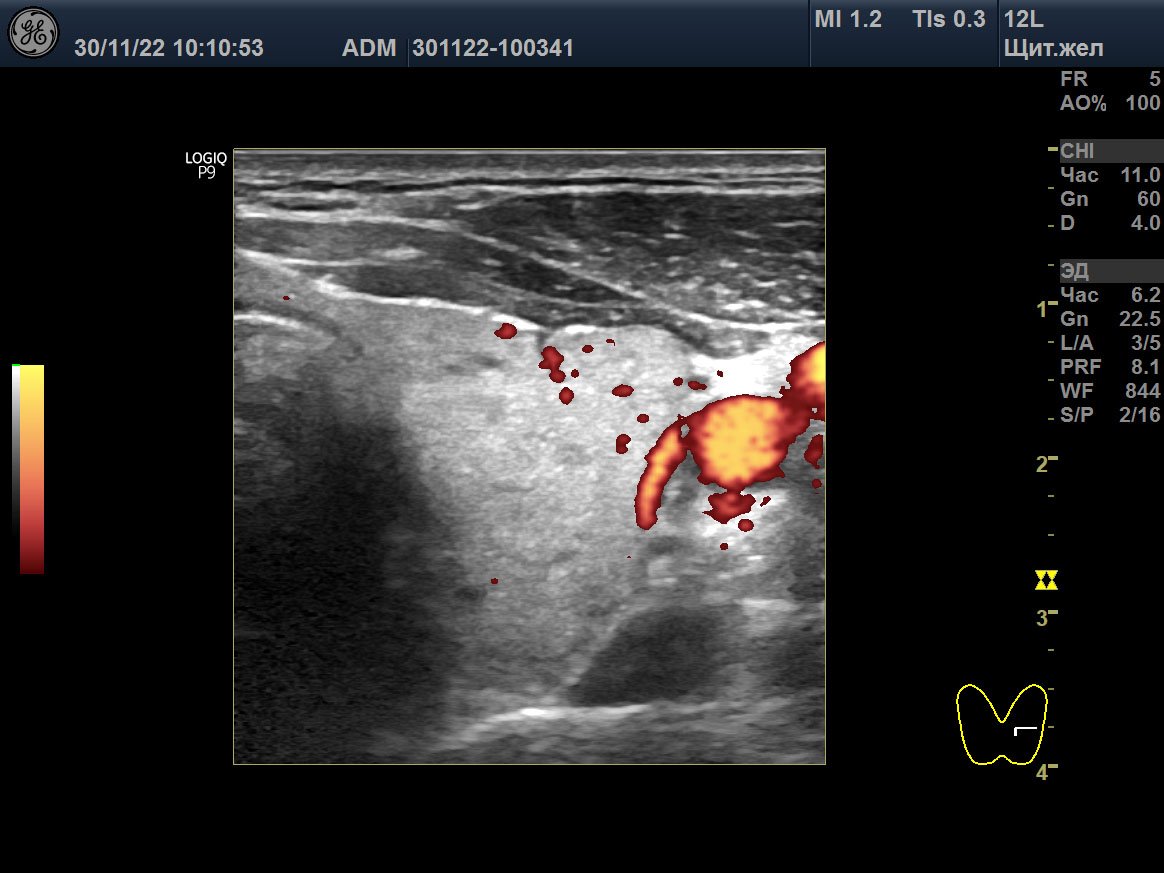

Изображения щитовидной железы пациента в режиме Допплера. A, B, C ― до лечения (15 мая 2018), и D, E, F после лечения (23 августа 2021). A, D ― поперечная проекция левой доли. B, E ― продольная проекция левой доли. C, F ― SPV STA слева.

Вместе с тем, в августе 2021, при нормальном гормональном обмене и АТ-рТТГ 0,3 Ед/л (<1,5), объём щитовидной железы остался прежним (30,4 мл), у дорсального края в обеих долях сохранялись некоторые признаки отёка стромы, интенсивность кровотока с двух сторон в очень малой мере была усилена, улучшилась SPV STA – 27 cm/sec справа и 39 cm/sec слева (таблица 2; рисунок: D, E, F). В декабре 2022 ультразвук показал подобные признаки с незначительным улучшением: объем щитовидной 24 мл и преобладание изоэхогенной паренхимы.